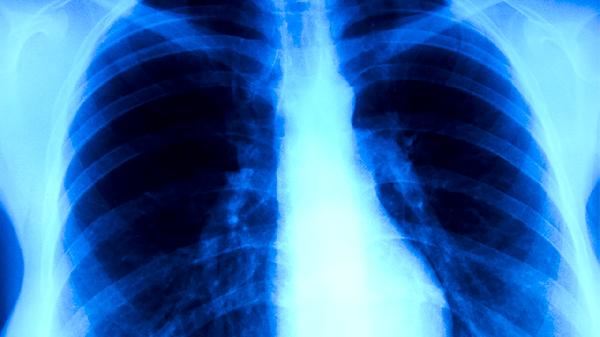

肺结核疾病都有哪些传染途径

肺结核主要通过呼吸道飞沫传播,常见传染途径包括直接接触患者咳嗽或打喷嚏产生的飞沫、吸入含结核杆菌的空气尘埃以及密切接触患者的痰液等分泌物。肺结核是由结核分枝杆菌引起的慢性传染病,病原体可侵犯全身多个器官,但以肺部感染最为常见。